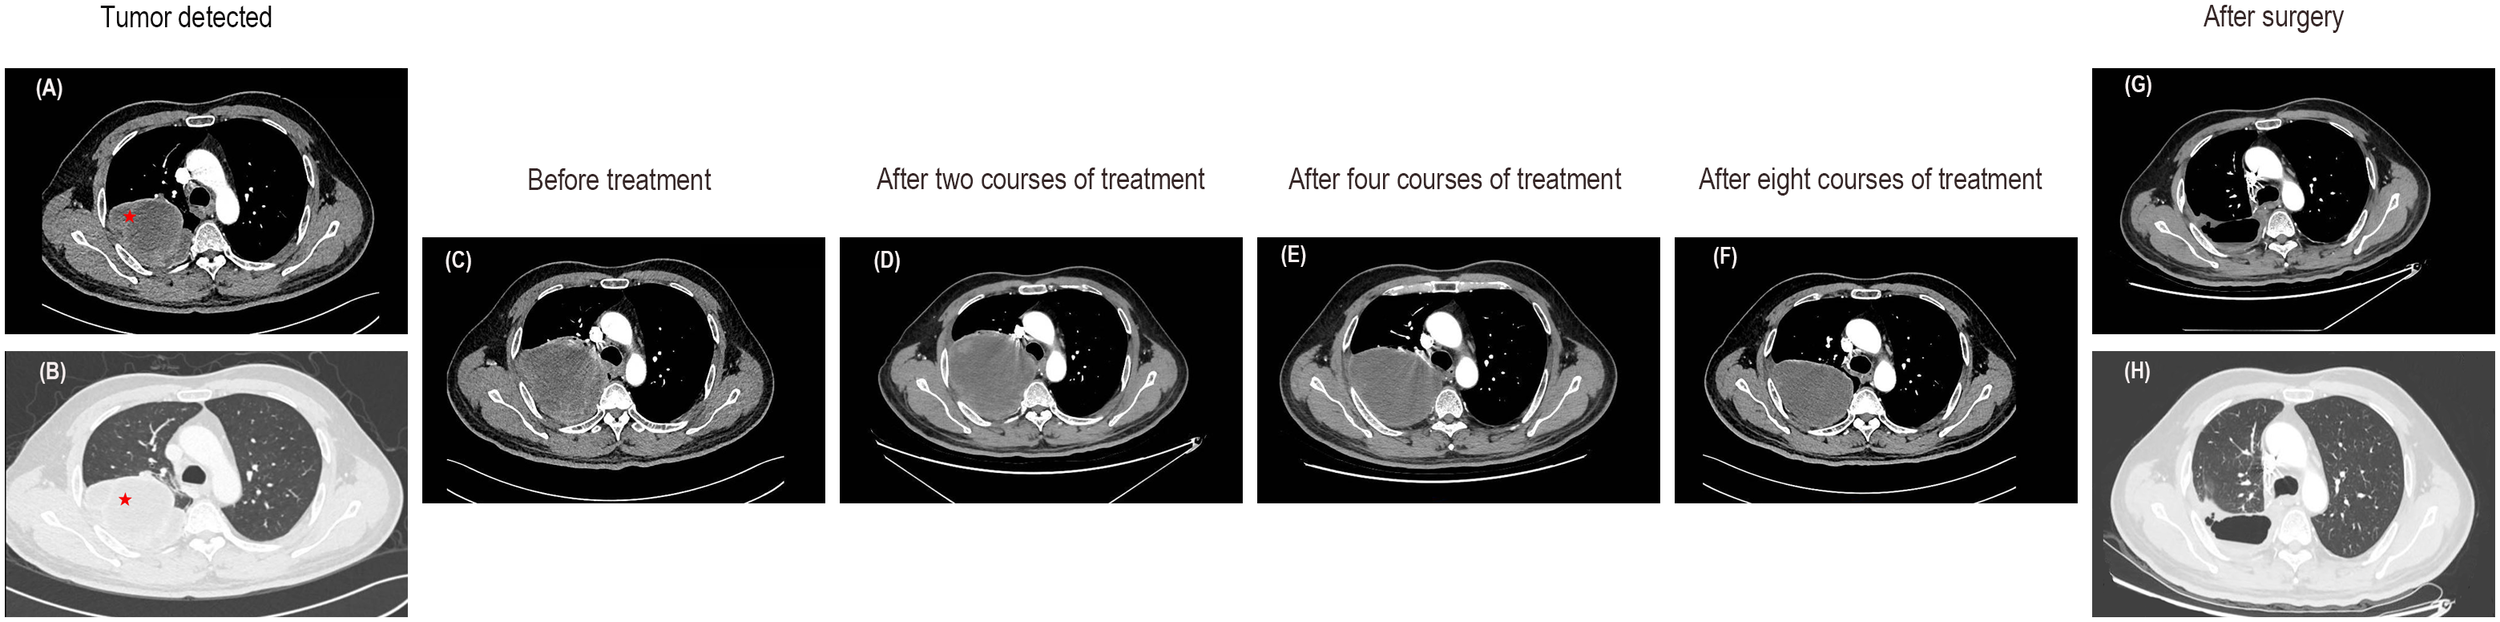

In November 2022, a chest computed tomography (CT) scan revealed a massive tumor in the right upper lobe measuring 91x80x137mm, raising suspicions of lung cancer. Enlargement of the right hilar and mediastinal lymph nodes was noted, along with a local invasion in the right 4th posterior rib (Figures 1A, B). The patient presented with normal mental status, right-sided rib pain, occasional bloody sputum in cough, and no complaints of wheezing or chest tightness. There had been no significant changes in recent body weight.

Figure 1

Enhanced CT images of the lung mass. (A, B) CT images at the time of tumor detection. (C) The CT images before any treatment. (D) Enhanced CT scans after two courses of treatment indicated a slightly enlarged tumor with an overall stable efficacy. (E) A subsequent CT scan after the fourth course of treatment showed stable disease. (F) The CT images after eight courses of treatment suggested a decrease in tumor size. (G, H) Enhanced CT revealed no tumor recurrence after surgery.

In this case, the patient presented with a massive right upper lung mass. An enhanced CT scan revealed an increase in the size of the right upper lobe pulmonary sarcomatoid carcinoma (107X95X160mm) compared to previous scans, along with enlarged right hilar and mediastinal lymph nodes, and slight progression, with local invasion into the chest wall and ribs, similar to previous findings (Figure 1C). Following consultation with thoracic surgeons, it was determined that, due to the tumor’s enormous size and local invasion into the chest wall and ribs, surgical intervention was not indicated at this time. Therefore, the initial treatment plan involved neoadjuvant chemotherapy, with the possibility of reassessing surgical options after tumor reduction. In terms of oncological treatment, a regimen combining chemotherapy and targeted therapy was considered, and further treatment options would be determined based on its effectiveness. With the patient’s and family’s consent, the first round of chemotherapy combined with targeted therapy was administered. The specific medications used were docetaxel (140mg on day 1) combined with cisplatin (50mg on days 1-2, 40mg on day 3) and bevacizumab(500mg on day 1), with every 21 days as one cycle. Starting in the second course of treatment and based on the genetic testing results and after consulting with the patient and family, the more cost-effective immune checkpoint inhibitor (ICI), tislelizumab (200mg on day 1), was ultimately selected. Thus, immunotherapy was introduced in addition to the existing chemotherapy and targeted therapy regimen. A follow-up CT scan showed stable disease (the tumor slightly increased in size to 114X104X160mm) (Figure 1D). During the fourth course of treatment, considering the side effects of docetaxel and cisplatin, the chemotherapy regimen was changed to a safer option, single-agent albumin-bound paclitaxel. The specific medications used were albumin-bound paclitaxel (400mg on day 1) combined with bevacizumab (500mg on day 1) and tislelizumab (200mg on day 1), with every 21 days as one cycle. A subsequent CT scan continued to show stable disease (a reduction in the size of the tumor to 109X90X152mm) (Figure 1E). During the fifth course of treatment, the original treatment plan was continued for one additional cycle. After completing six cycles of chemotherapy, the treatment was discontinued. Tislelizumab monotherapy was administered during the seventh and eighth courses of treatment. A follow-up CT scan showed stable disease (the size of the tumor was reduced to 100X76X128mm) and the majority of the mass appeared cystic without enhancement (Figure 1F). The CT scan demonstrated a reduction in tumor size with low-density areas and no enhancement within the tumor. Following a collaborative assessment by the radiologist and thoracic surgeon, there was a consensus that significant tissue necrosis was present. It was recommended that the patient undergo positron emission tomography-computed tomography (PET-CT) to assess the metabolic status of the tumor. However, the patient declined the examination due to financial reasons. Considering the patient’s current stable condition, it was determined that further conservative internal medicine treatment would not provide additional benefits. Therefore, after consultation with the thoracic surgery team, surgical treatment was recommended. With the patient’s consent, the patient underwent video-assisted thoracoscopic surgery.

Currently, the patient is in good physical condition and continues to attend regular outpatient follow-up visits. In the most recent follow-up at one month postoperatively, the CT scan showed the following findings: a right upper lobe pulmonary sarcomatoid carcinoma post-surgery, irregular band-like opacities in the surgical area, and thickening of the right interlobar fissure and pleura. Regular follow-up with CT or PET-CT scans is recommended. Rib changes were essentially unchanged from before and some mediastinal lymph nodes appeared slightly enlarged. Due to inflammation in the left lower lobe, a post-treatment follow-up was recommended (Figures 1G, H). To consolidate the treatment effect, immunotherapy was continued in the third month postoperatively with a regimen of tislelizumab. The patient’s overall diagnostic and treatment process is shown in Figure 4.